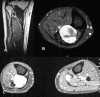

Case presentation: This is a report of three patients who presented with a painful swollen leg and were initially treated as a deep vein thrombosis or a baker's cyst, but later diagnosed as a pleomorphic sarcoma, a malignant giant cell tumor of the muscle and a myxoid liposarcoma. A brief review of such similar reports and the relevant literature is presented.